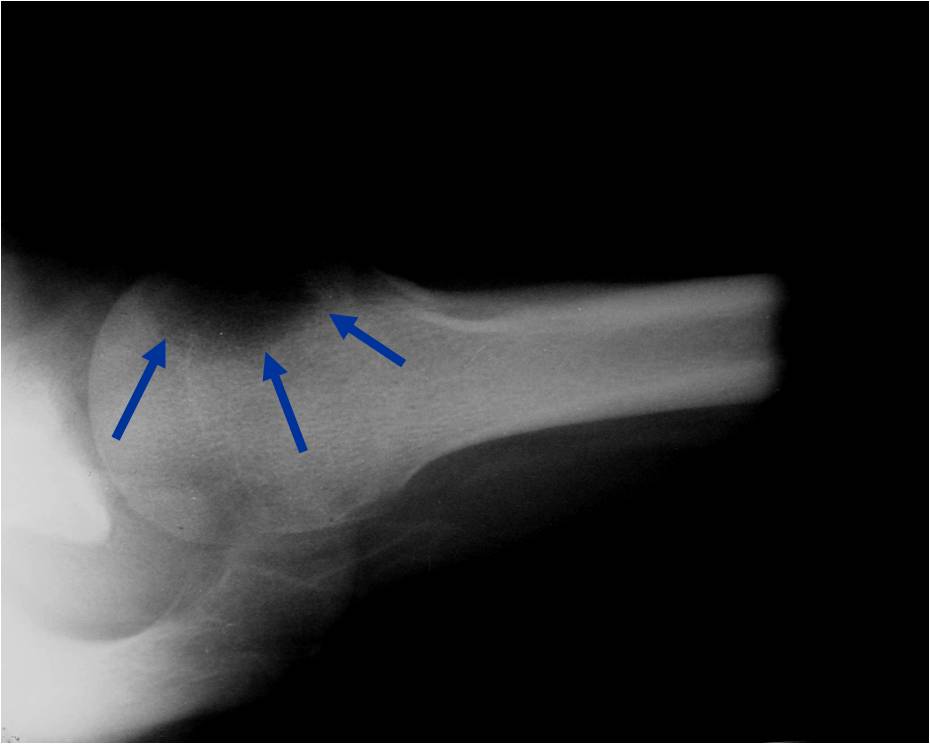

Treatment of a Chondroblastoma of Proximal Humerus with Intralesional Curettage Resection, Cryosurgery and Bone Grafting

- intralesional curettage resection and bone grafting most common treatment

- Cement and internal fixation may also be used to fill the defect after removal for selected patients

- High risk of local recurrence after curettage alone

- Local adjuvants such as cryosurgery (liquid nitrogen application) may be considered to decrease the risk of local recurrence